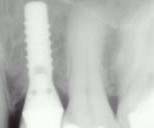

Fallbeispiel: Unterkieferfreiendsituation -> Implantate bei 34, 35 und 36 (Patientenfall Praxis Dr. Lauerer - Rö nach OP und nach 3 Monaten)